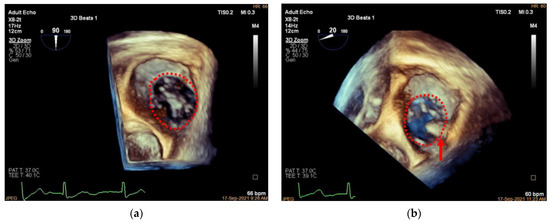

2. Transcatheter Tricuspid Annuloplasty

3.4. Adjustment of the Clip Arm and Clamping of Annular Tissue